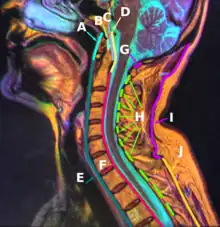

B: Apical ligament of dens